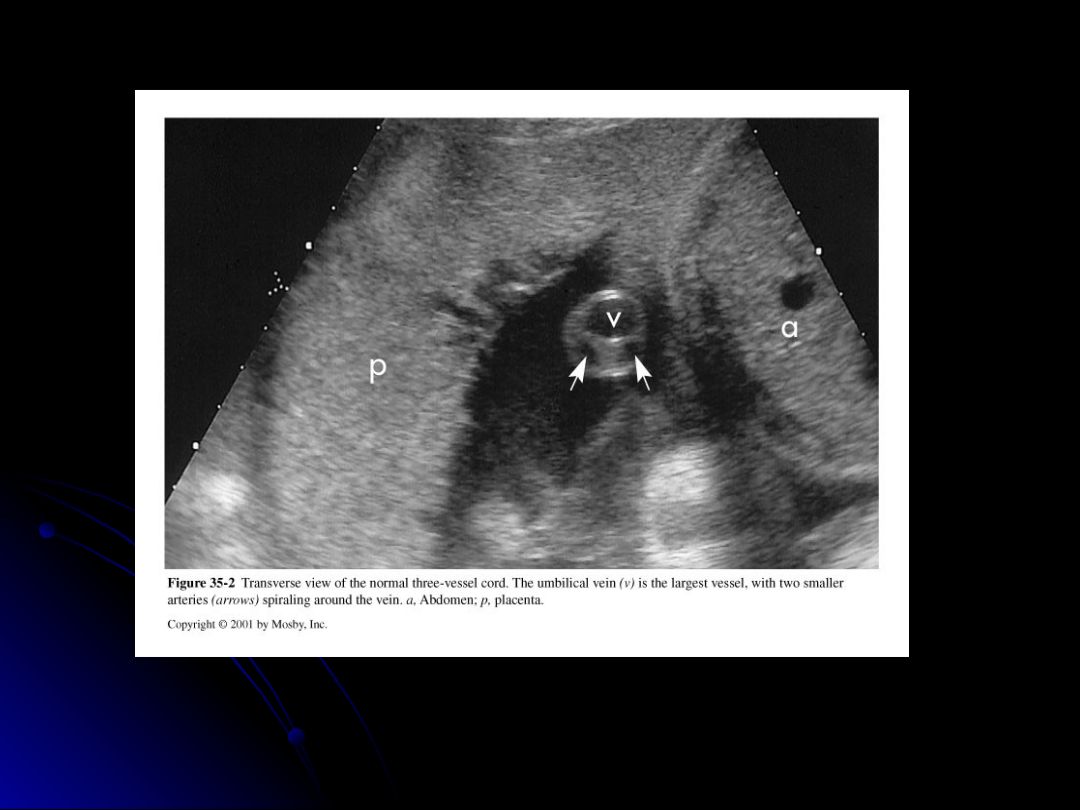

In the ultrasound image, which vessel is identified as the largest within the umbilical cord?

Two umbilical arteries and one umbilical vein